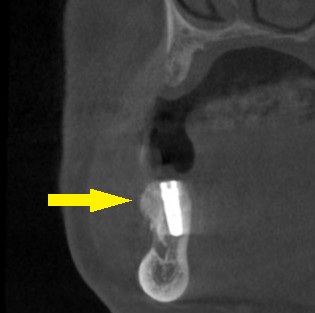

CTで見ると、歯肉がやせているのと同じように、骨も細くなってしまっていました(下の写真2段目)。

骨幅が狭いので、インプラント埋入と同時に、外側に人工骨を補填して、骨幅を増やす、骨造成術の併用が必要であると説明させていただきました。